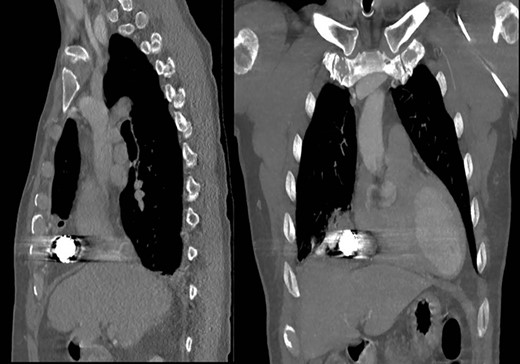

Representative axial and sagittal images from the patient’s CT scan on Day 7 after initial operative intervention. The white arrows on both images show subcutaneous and intrathoracic air, concerning for an empyema.

Subsequent review of bean bag projectiles and discussion with the law enforcement officers monitoring the patient revealed that the bean bag projectile included nonmetal components. Out of concern for infection risk, the surgical team performed video-assisted thoracoscopic surgery (VATS) on hospital Day 3 whereby the projectile was successfully removed (Fig. 3). Upon intra-operative inspection, the right middle lobe was contused but not actively bleeding, so no further intervention was performed, and a new chest tube was placed. On post-operative day (POD) 3, the chest tube was removed; however, on POD 6 purulent drainage was observed from the previous bean bag entry wound, and laboratory evaluation revealed a leukocytosis to 21.0 K/mm3. The clinicians irrigated the wound at the bedside and initiated antibiotics treatment. Due to persistent leukocytosis and drainage of purulent fluid from the wound, the clinicians obtained a CT scan on POD 7, which showed a complex right pleural effusion that communicated with a small pocket of fluid in the chest wall, concerning for an empyema (Fig. 4). The following day, the surgeons performed VATS decortication, removing a significant amount of purulent pleural fluid and fibrinous exudate and placing two chest tubes. Culture of the pleural fluid grew Staphylococcus aureus. By POD 11/3, the patient had a persistent right-sided effusion, which the team treated with intrapleural tPA/Dornase infused via previously placed chest tubes. By POD 20/12, the patient’s leukocytosis and right-sided effusion had resolved, and both chest tubes were removed. He was discharged the subsequent day and has not returned to our facility since then.